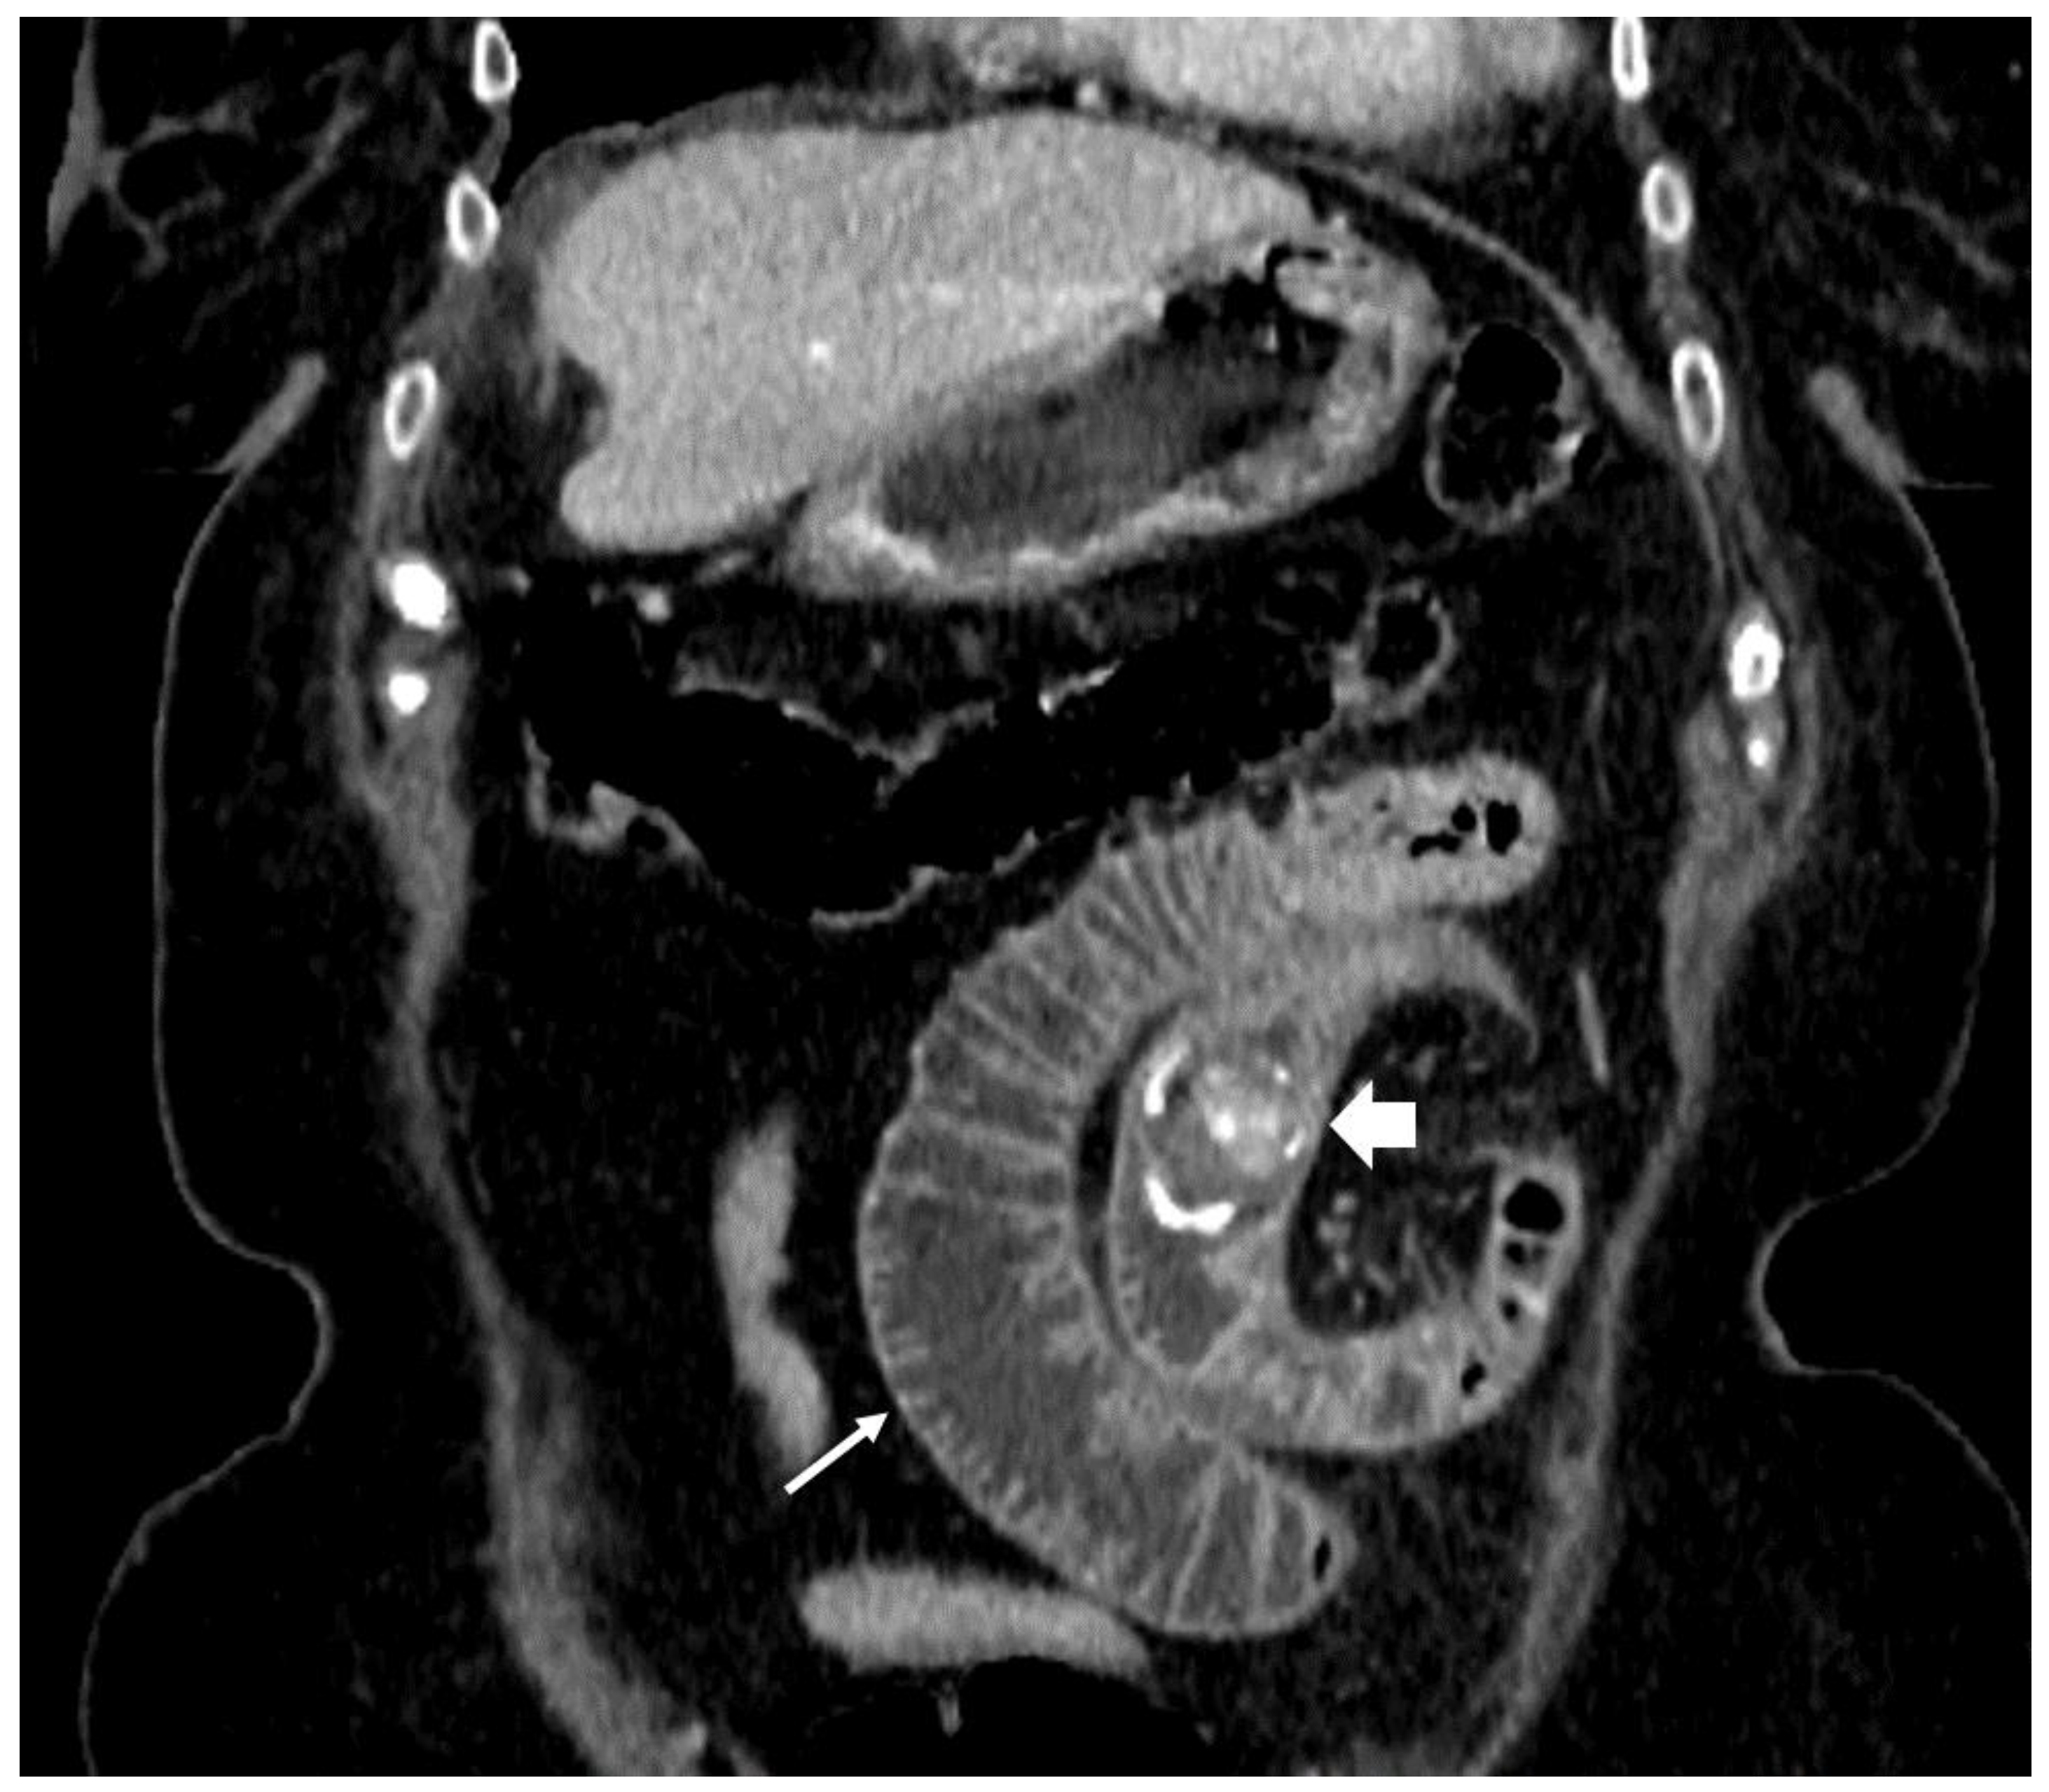

| F, 69 | 12 | III | Colonoscopy | 115 | Sigmoid colon | 5 × 4 cm | - | 10 | Good: recovery |